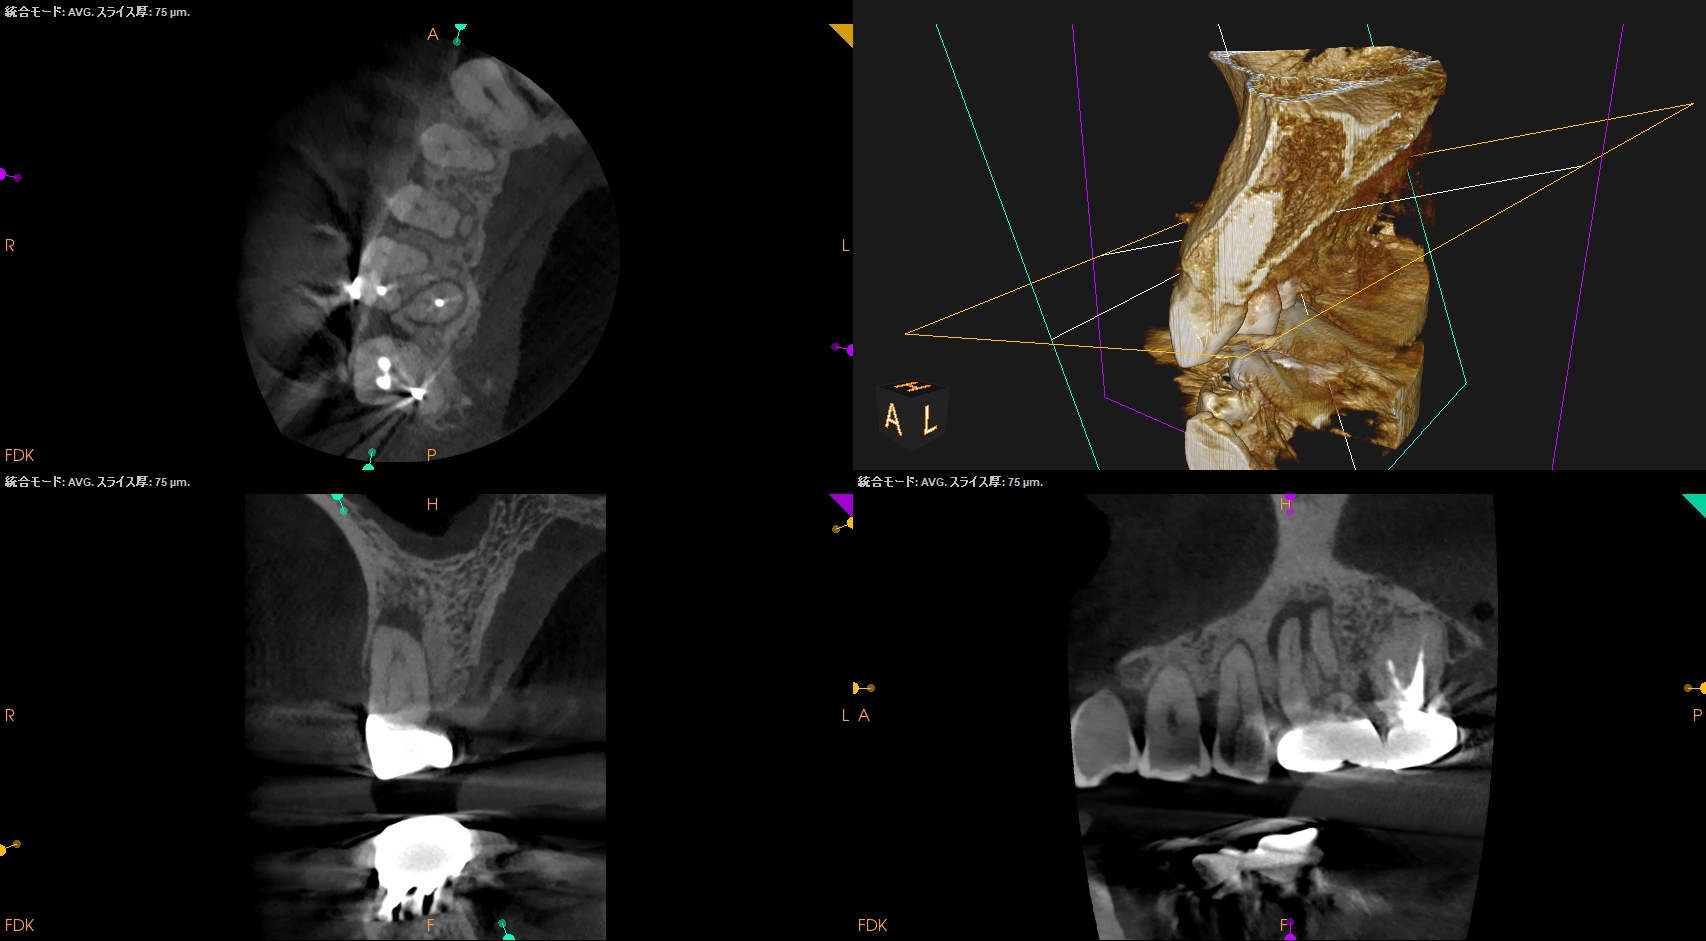

Pre-op CBCT(2024.11.25)

MB

DB

P

B

P根以外のMB,DBには根尖病変がありSinus tractがある。

ということは…

MB+DB Apicoectomyだ。